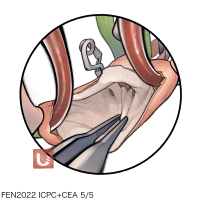

FEN2022シリーズ